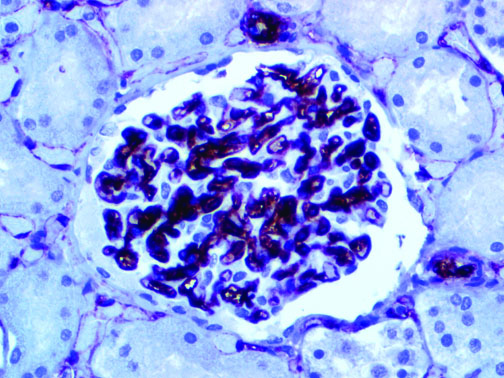

It is the ICU physician who is most likely to witness one of the deadliest manifestations of the abnormal immunological response, the cytokine storm syndrome (CSS). This response is also referred to by some as the cytokine release syndrome (CRS). CSS is characterized by continuous activation and expansion of macrophage and lymphocyte populations, which secrete large amounts of cytokines, causing the cytokine storm. This massive cytokine release is akin to hemophagocytic lymphohistiocytosis (HLH) disease, a syndrome characterized by initial unchecked and persistent activation of cytotoxic T lymphocytes and NK cells.

Clinical and laboratory manifestations of HLH include fever, enlarged liver and/or spleen, neurologic dysfunction, coagulopathy, liver dysfunction, cytopenias (i.e., low levels of erythrocytes, leukocytes, and/or platelets), hypertriglyceridemia, hyperferritinemia, hemophagocytosis, and eventually diminished NK cell activity as the immune system becomes progressively paralyzed. HLH can be familial (primary HLH) or secondary to another disease process (sHLH), such as rheumatic disease, in which it is referred to as macrophage activation syndrome (MAS, characterized by elevated ferritin).